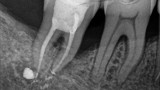

Bogata w płytki i leukocyty fibryna jest stosowana w regeneracji tkanek od ponad 15 lat. Pozytywny wpływ PRF (platelet-rich fibrin) na regenerację tkanek miękkich jest niewątpliwy, bezsporny i częściowo udowodniony w badaniach klinicznych i analizach biochemicznych. Wpływ PRF na regenerację tkanki kostnej jest obserwowany klinicznie, ale nadal niedostatecznie poznany jest mechanizm tego zjawiska.

Platelet- and leukocyte-rich-fibrin has been used in regeneration of tissue for more than 15 years. The positive influence of PRF on the regeneration of soft tissue is undoubtedly, without question and partially proven in clinical studies and biochemical analysis. Influence of PRF on regeneration of bone tissue is observed clinically but the mechanism of this phenomenon is still not sufficiently known.